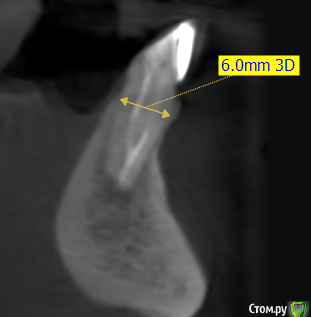

kramer Опубликовано 26 мая, 2020 Поделиться Опубликовано 26 мая, 2020 В общем, ситуация: 41, 42 бессимптомный периапикальный очаг, зуб 42 треснул. Биотип толстый. С точки зрения мезио-дистального расстояния влезает только 1 имплантат. Какой, на ваш взгляд, наиболее рациональный путь: а. Удаление обоих зубов, одномоментная имплантация 42, в последствии коронка с консолью б. Удаление обоих зубов, отсроченная имплантация в обл 42, в последствии коронка с консольюв. Удаление 41 с кюретажем, через пару месяцев удаление 42, одномоментная имплантация 42, в последствии коронка с консолью Ссылка на комментарий

red_butler Опубликовано 26 мая, 2020 Поделиться Опубликовано 26 мая, 2020 Я бы один поставил, одномоментно в позицию бокового резца 6 Ссылка на комментарий